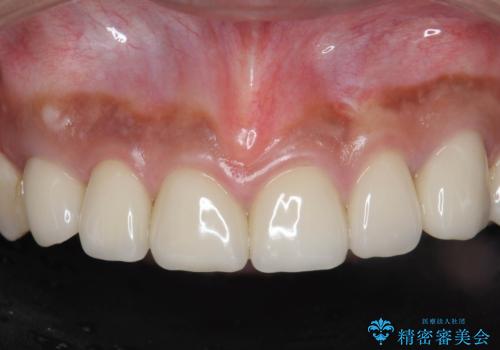

[ 歯ぐきから出血をする ] 歯周外科を伴うセラミックやりかえ治療